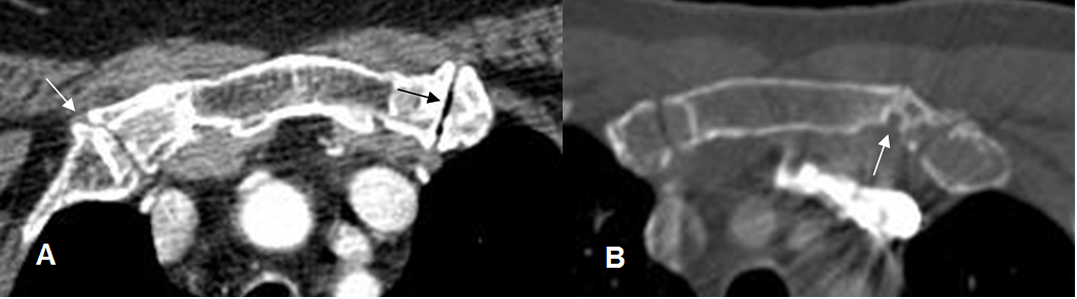

Fig 31A. Cambios degenerativos.

A: TAC axial. Pérdida del espacio articular y formación de osteofitos en articulaciones costoesternales, por artropatía degenerativa. En el lado izquierdo se aprecia fenómeno del vacío.

B: TAC axial. Cambios degenerativos con la presencia de quistes subcondrales.